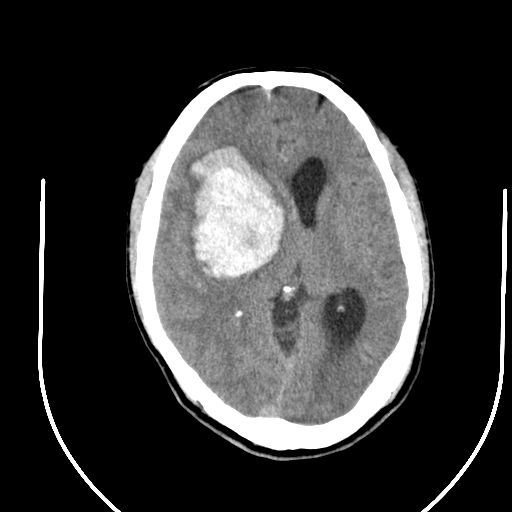

标题: CT24997:M,60Y,突发昏迷30分钟,有高血压病史。 [打印本页]

标题: CT24997:M,60Y,突发昏迷30分钟,有高血压病史。

右侧基底节区脑出血并破溃入脑室。

1右侧基底节脑出血伴脑干出血并破入脑室系统脑疝形成2梗阻性脑积水

1)右侧基底节脑出血伴脑干出血并破入脑室系统。2)大脑镰下疝。3)梗阻性脑积水。

1、右侧基底节脑出血伴脑干出血并破入脑室系统。

2、大脑镰下疝。

3、梗阻性脑积水。